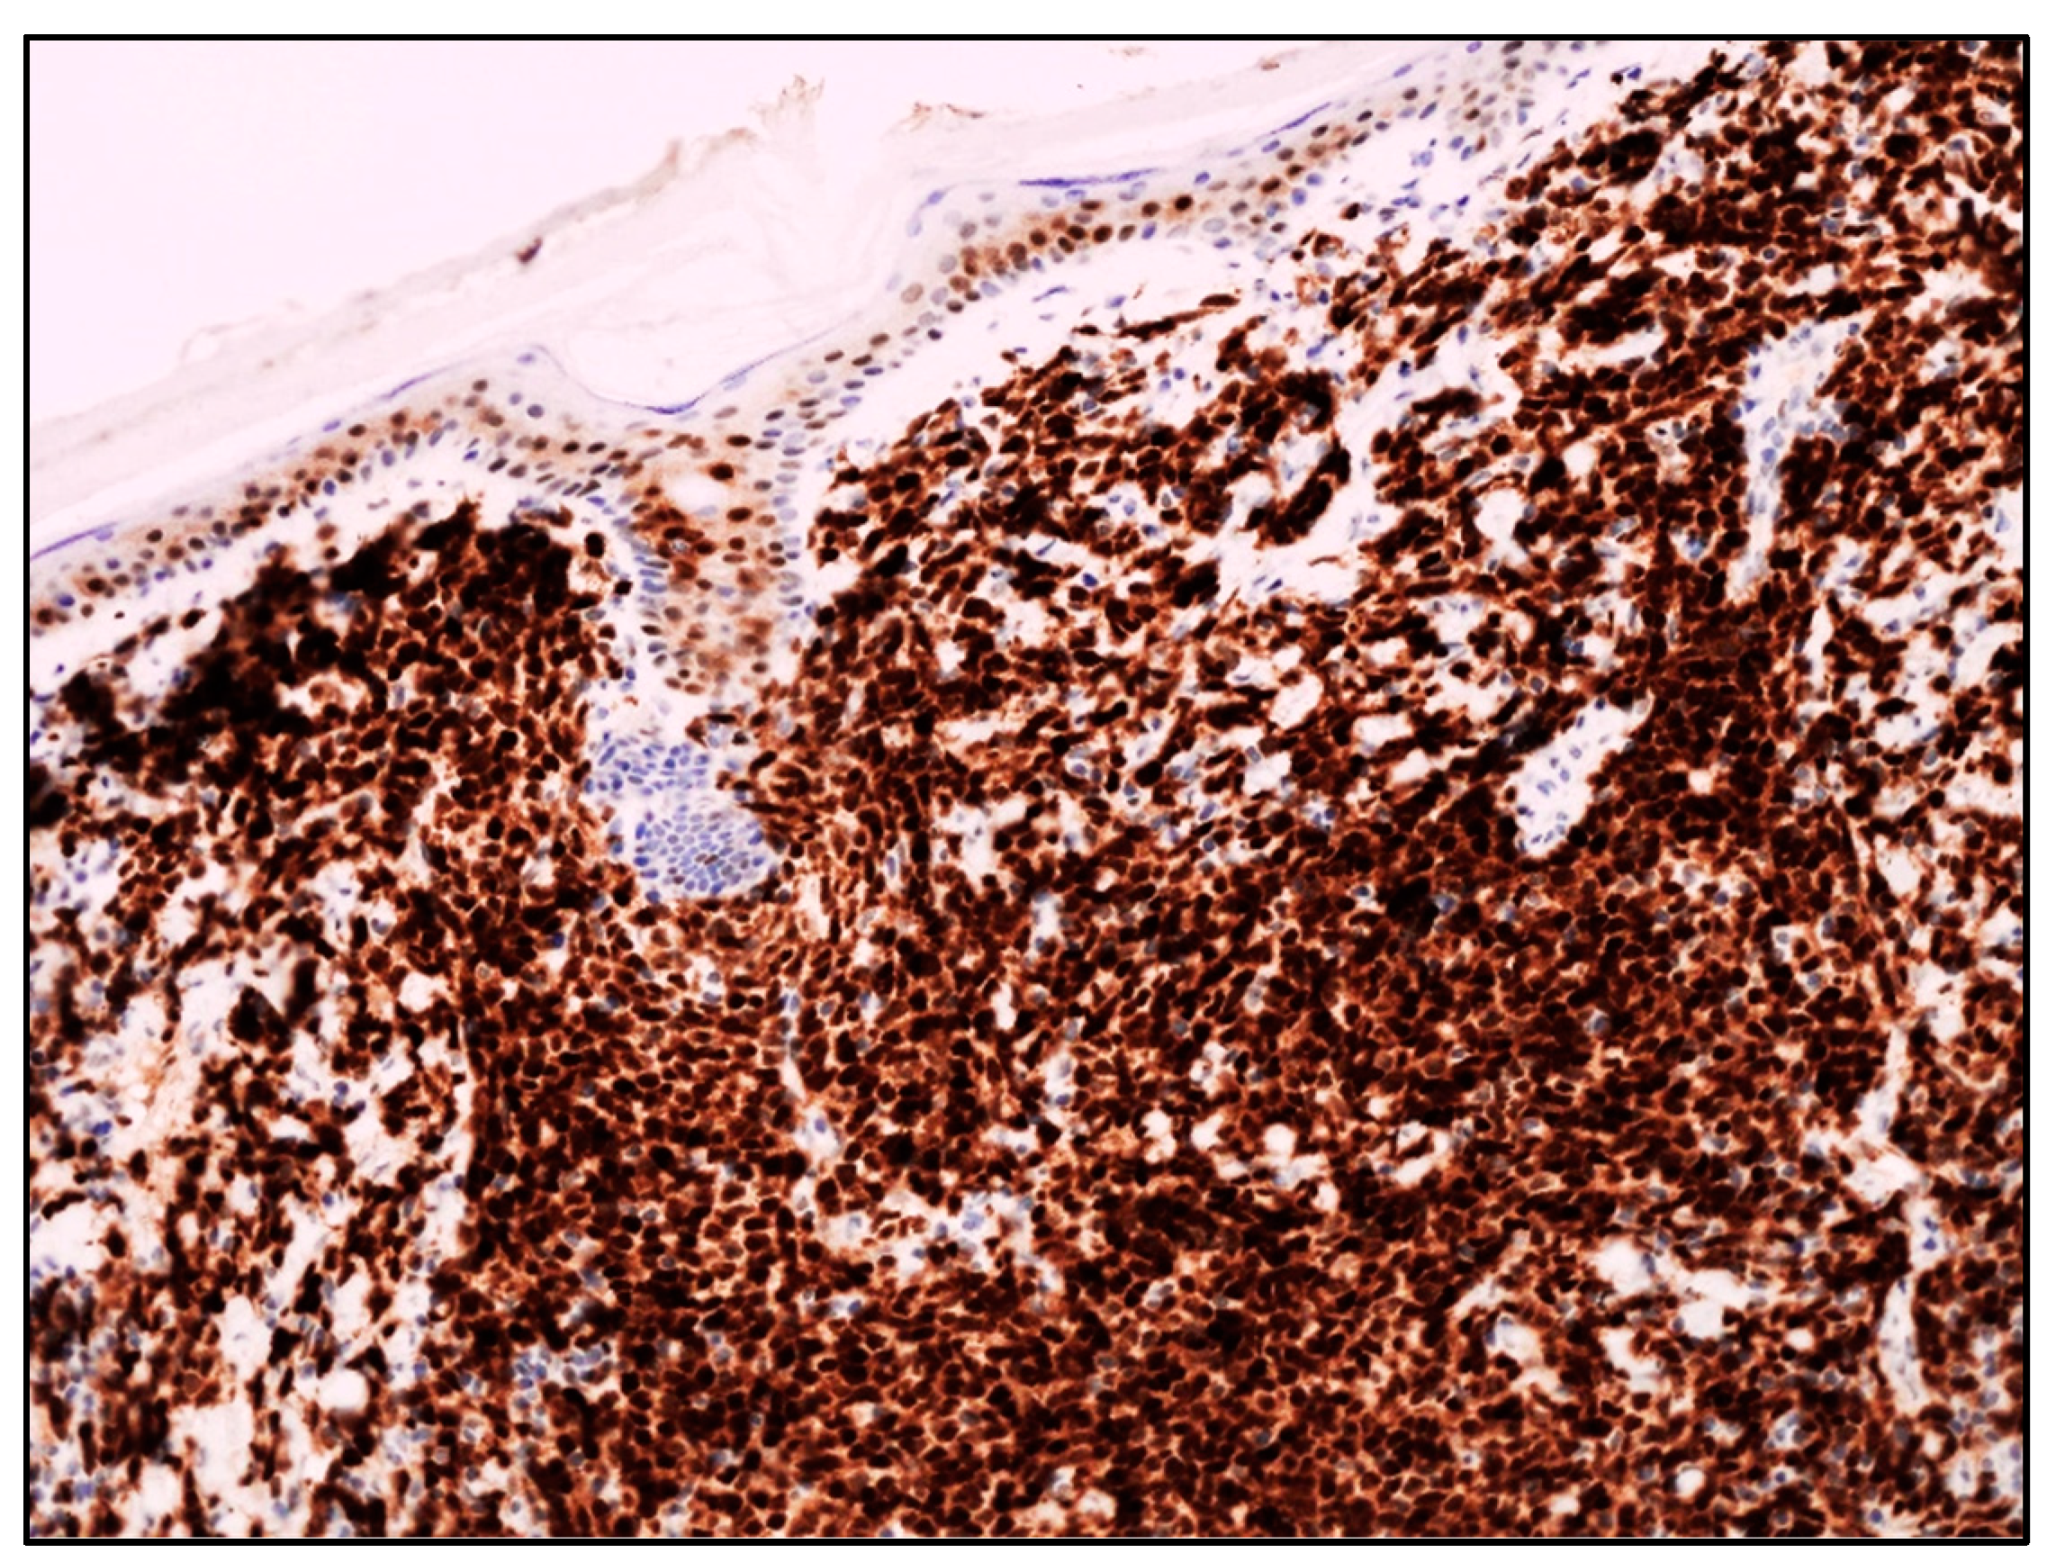

| Blastoid MCL | M:F = 3:1; late sixties | Solitary/multiple papules or nodules; often on extremities. Often previous history of MCL; skin lesions in recurrent and progressive disease | Diffuse dermal and subcutaneous tissue infiltrate; no epidermis and Grenz zone involvement. Monomorphic, medium-sized cells, round/oval nuclei, dispersed chromatin, inconspicuous nucleolus | Mature, naïve B-lymphocytes | CD20+, cyclin D1+, TdT−, CD3−, CD5+ (CD5 loss in 25-28% of blastoid MCL); aberrant expression of CD10, BCL6, CD23; TP53 overexpressed; high Ki67 | Poor. Intensive CT and immunotherapy plus ASCT; recently, anti CD19 CART cells, venetoclax, ibrutinib, acalabrutinib |

| B-LBL | F:M = 2:1 children young adults | Often solitary, firm papule or nodule on head and neck. Skin lesions in 15-33% of B-LBL; skin lesions associated with systemic disease | Dense dermal infiltrate; no epidermis and Grenz zone involvement; uniform, small, medium-sized cells, round/oval/convoluted nuclei, fine chromatin, barely visible nucleoli, scarce basophilic cytoplasm; numerous mitoses | Precursor B- lymphocytes | TdT+, CD34+, CD10+, PAX5+, cCD79alpha+, CD19+, CD22+, high Ki67 | Good prognosis in 70% of cases with B-lineage ALL-type. Multiagent CT. |

| T-LBL | M:F = 3:1 children young adults | Multiple papules or nodules on head and neck (83.3%); different anatomic areas in 41.7%. Skin lesions rare in T-LBL (4.3% of cases); skin lesions secondary to T-LBL in mediastinum or lymph nodes | Histology identical to B-LBL | Precursor T-lymphocytes | TdT+, CD34+, CD1a+, CD99+, CD117+, cCD3+, sCD3+, CD2+, CD5+, CD7+, aberrant cCD79alpha+, aberrant myeloid markers+ | Cutaneous T-LBL are rare, but with a worse outcome compared to cutaneous B-LBL despite multiagent CT. |